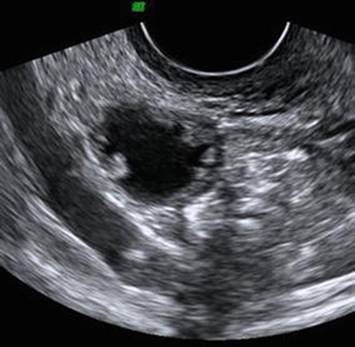

Imaging is not required for the diagnosis of PID, and most patients will have normal imaging. Transvaginal ultrasound in patients with PID may reveal thickened fallopian tubes [15]. Less commonly, the “cogwheel” sign may be seen, which refers to a sonolucent cogwheel structure visible on cross section of an inflamed fallopian tube, representing the swollen walls and mucosal folds projecting into the lumen (Fig. 6.2) [16, 17].

Fig. 6.2

Ultrasound image illustrating the cogwheel sign (Reprinted from Romosan and Valentin [16], Figure 3, with kind permission from Springer Science and Business Media)